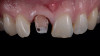

(5.) Case 1: Discolored stump and resin core immediately following sectioning and removal of the existing ceramic restoration.

Figure 5

(6.) Case 2: Discolored stump immediately following sectioning and removal of the existing ceramic restoration.

Figure 6

The prosthetic and endodontic protocols were nearly identical for all phases of treatment in both cases. At the first operative visit, the existing ceramic crown was carefully sectioned and removed (Figure 5 and Figure 6). This was followed by the removal of any existing supragingival core materials in the first case. Next, the highly chromatic underlying natural stump shade was recorded, and a provisional restoration was fabricated and luted with temporary cement. Each patient was then immediately dismissed to the endodontist for same-day elective root canal therapy and internal bleaching treatment with the walking bleach technique.